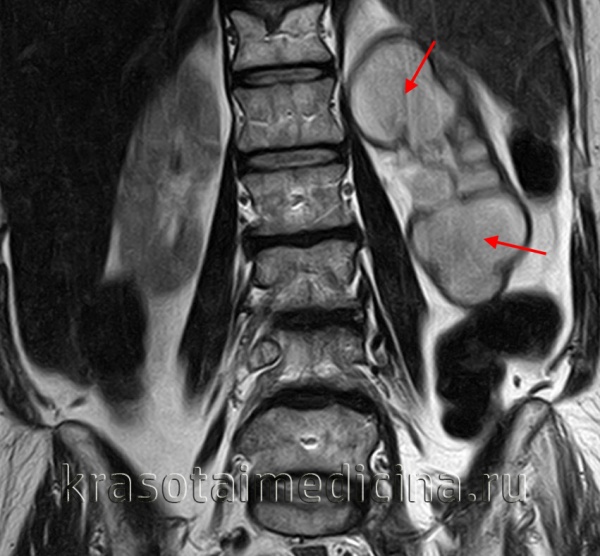

МРТ ОБП. Выраженное расширение лоханки и чашечек левой почки с атрофическими изменениями ее паренхимы.

По времени развития гидронефроз может быть первичным (врожденным) или приобретенным (динамическим). По тяжести течения выделяется легкий, умеренный и тяжелый гидронефроз; по локализации – односторонний и двусторонний. В практической урологии с одинаковой частотой встречается гидронефроз правой и левой почки; двусторонняя гидронефротическая трансформация наблюдается в 5-9% случаев.